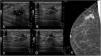

We included patients with histologically confirmed nonpalpable malignant lesions treated by surgery in 2015 or 2016. Patients were randomly assigned to presurgical marking with metallic clips (Group A) or with 125I seeds (Group B). In both groups, marking was guided by ultrasound and/or mammography depending on the radiologic characteristics of the lesion. During surgery, a gamma probe was used and afterward the presence of seeds in the surgical specimen was checked radiologically. In the histological analysis, the absence of tumour in the stain was considered free margins. We analysed the following variables: age, lesion characteristics (laterality, mean size on MRI and in the surgical specimen, radiological type), and presence/absence of free margins.